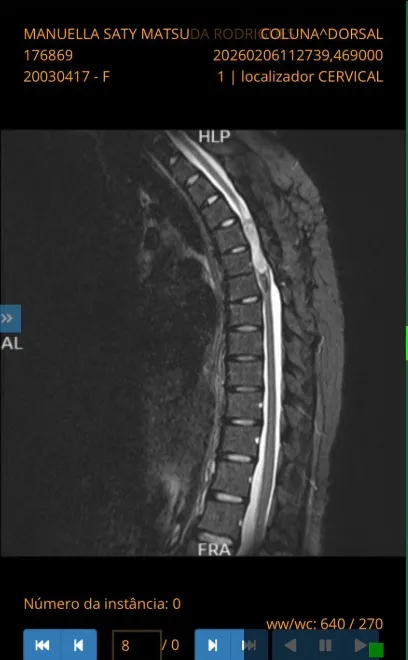

Em 2026, o quadro voltou a se agravar. Exames recentes indicaram o crescimento de um novo tumor intramedular, agora com cerca de 5,4 centímetros, localizado predominantemente na vértebra T2. A condição tem causado dores intensas e a perda total da sensibilidade e dos movimentos nos membros inferiores.

Ressonância que apresentou novo tumor na jovem